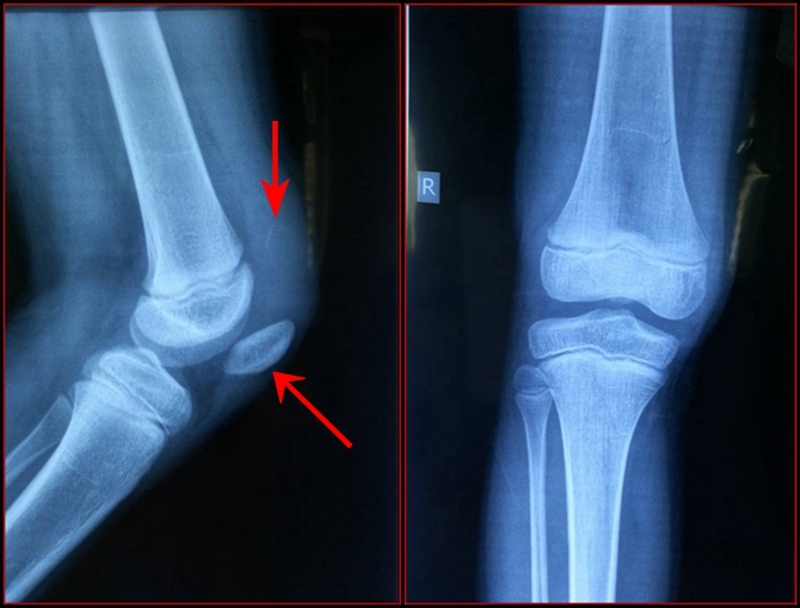

图1 受伤当时X线片

患儿,男,10岁,主因右膝部摔伤后石膏固定3周入院。

现病史:患儿于3周前下台阶时踩空而不慎摔伤右膝,当即感右膝肿胀、疼痛、不敢活动。于当地县医院就诊,行右膝拍片后诊为“右膝软组织损伤”,建议石膏固定3周。患儿于伤后3周门诊复查,再次拍片后诊为“右髌骨骨折”,建议手术治疗,家属为进一步诊治来我院门诊,门诊以“右髌骨套状撕脱骨折”收入院。